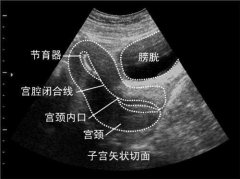

長在子宮頸上的“青春痘” 大為醫用B超為您淺析

現在很多朋友都有了自我保健的意識,主動體檢的人越來越多,宮頸納氏囊腫(簡稱納囊)也因此而更多的在超聲檢查中被發現。...